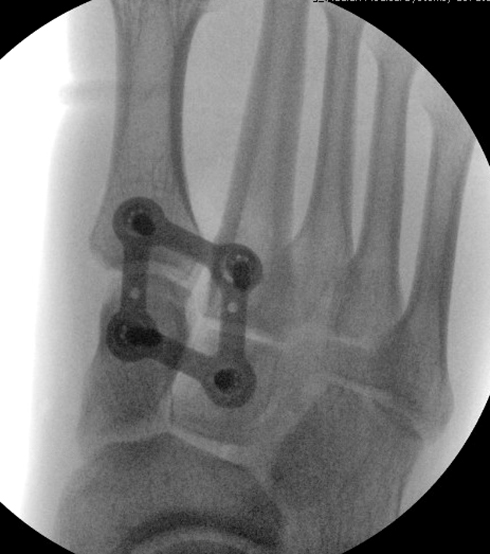

TOTAL ANKLE REPLACEMENT :: ORIF CALCANEUS :: ORIF ANKLE FRACTURE DISLOCATION :: COMPLEX BUNION AND LESSER TOE CORRECTION :: TALUS FRACTURE -1 :: TALUS FRACTURE -2 :: LISFRANC REPAIR :: COMPLEX TRIPLE ARTHRODESIS 1 :: COMPLEX TRIPLE ARTHRODESIS 2 :: MINIMALLY INVASIVE BUNION REPAIR 1 :: MINIMALLY INVASIVE BUNION REPAIR 2 :: ARTHROSCOPIC CARTILAGE REPAIR :: TENEX SPUR DEBRIDEMENT :: Haglunds Debridement and Achilles Repair